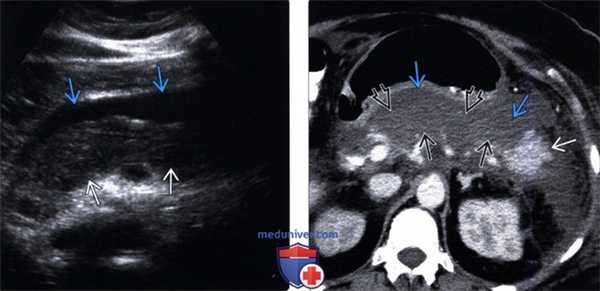

(Левый) На поперечном срединном УЗ срезе в ложе поджелудочной железы определяется гетерогенное скопление, содержащее нежидкостные фрагменты, что указывает на развитие некроза поджелудочной железы и перипанкреатических тканей.

(Правый) У этого же пациента при КТ с контрастным усилением на поперечной томограмме наблюдается полное отсутствие контрастирования тела и хвоста поджелудочной железы, что характерно для панкреонекроза. Также определяется пери панкреатическое скопление жидкости, содержащее нежидкостные фрагменты, это указывает на острый некроз перипанкреатических тканей и формирование очага острого некроза.